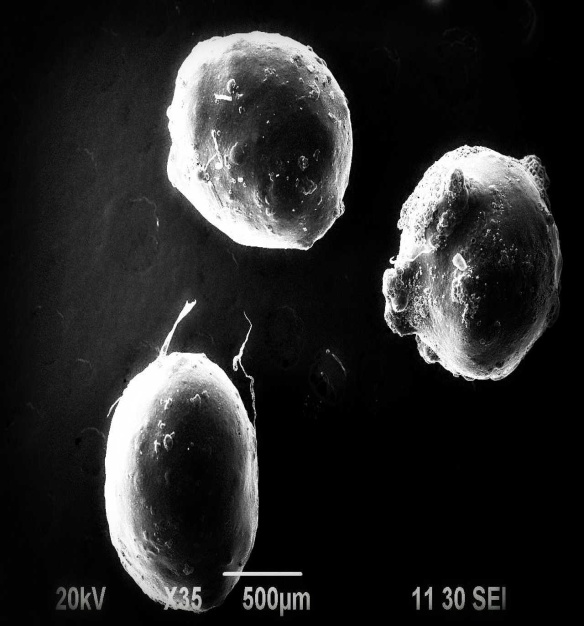

Surface morphology study with the help of scanning electron microscope (SEM)

Surface nature of microspheres was examined with the help of Scanning Electron Microscope (JEOL, JSM-6490 LA, Japan). The microspheres were dried completely before examination SEM was done at different magnifications of 20 kV X 40, 20 kV X 100, 20 kV X 200, 20 kV X 500 to examine the surface picture and size of the microcapsules that changed from formula to formula shown in figure 6. The working distances were 10 and 11 inches.

Effect of polymer concentration on surface morphology of prepared microspheres

The surface topography of the microspheres was investigated by SEM. As seen in fig. 6, they were spherical in shape and exhibited porous surfaces. The SEM of drug-loaded microspheres in fig. 6b had rough surface due to higher concentration of drug in the microspheres as compared to the blank microspheres fig. 2a. Surface study of the microspheres after release study showed bigger pores (fig. 2c) suggesting that the drug was released through pores and the mechanism of drug release was diffusion controlled.

a. |

b. |

c. |

Fig. 6: Scanning Electron Microscopic photograph of microspheres of a) blank microspheres b) formulation B2 and c) formulation A3